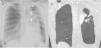

La patología de las vías respiratorias de medio calibre (bronquios segmentarios y subsegmentarios) es común y se presenta con síntomas respiratorios poco específicos, como tos, infecciones de repetición y en ocasiones hemoptisis. La dilatación permanente del árbol bronquial se conoce como «bronquiectasia» y representa un reto diagnóstico. El análisis de la distribución regional de las bronquiectasias en los diferentes lóbulos pulmonares es la guía diagnóstica más útil. El objetivo de este trabajo es describir los hallazgos de imagen de las bronquiectasias y sus diferentes tipos, revisar las situaciones más comunes y proponer un algoritmo diagnóstico basado en su distribución anatómica. Las bronquiectasias son un hallazgo frecuente, resultado de un amplio espectro de enfermedades. Los estudios de imagen desempeñan un papel esencial en su detección, clasificación y orientación diagnóstica hacia la patología subyacente

Diseases that involve the medium caliber airways (segmental and subsegmental bronchi) are common and present clinically with nonspecific respiratory symptoms such as cough, recurrent respiratory infections and occasionally, hemoptysis. The abnormal and irreversible dilation of bronchi is known as “bronchiectasis”. The diagnosis can be challenging and the analysis of the regional distribution of the bronchiectasis is the most useful diagnostic guide. The objective of this manuscript is to describe the main imaging findings of bronchiectasis and their classification, review the diseases that most commonly present with this abnormality, and provide an approach to the diagnosis based on their imaging appearance and anatomic distribution. Bronchiectasis is a frequent finding that may result from a broad range of disorders. Imaging plays a paramount role in diagnosis, both in the detection and classification, and in the diagnosis of the underlying pathology.